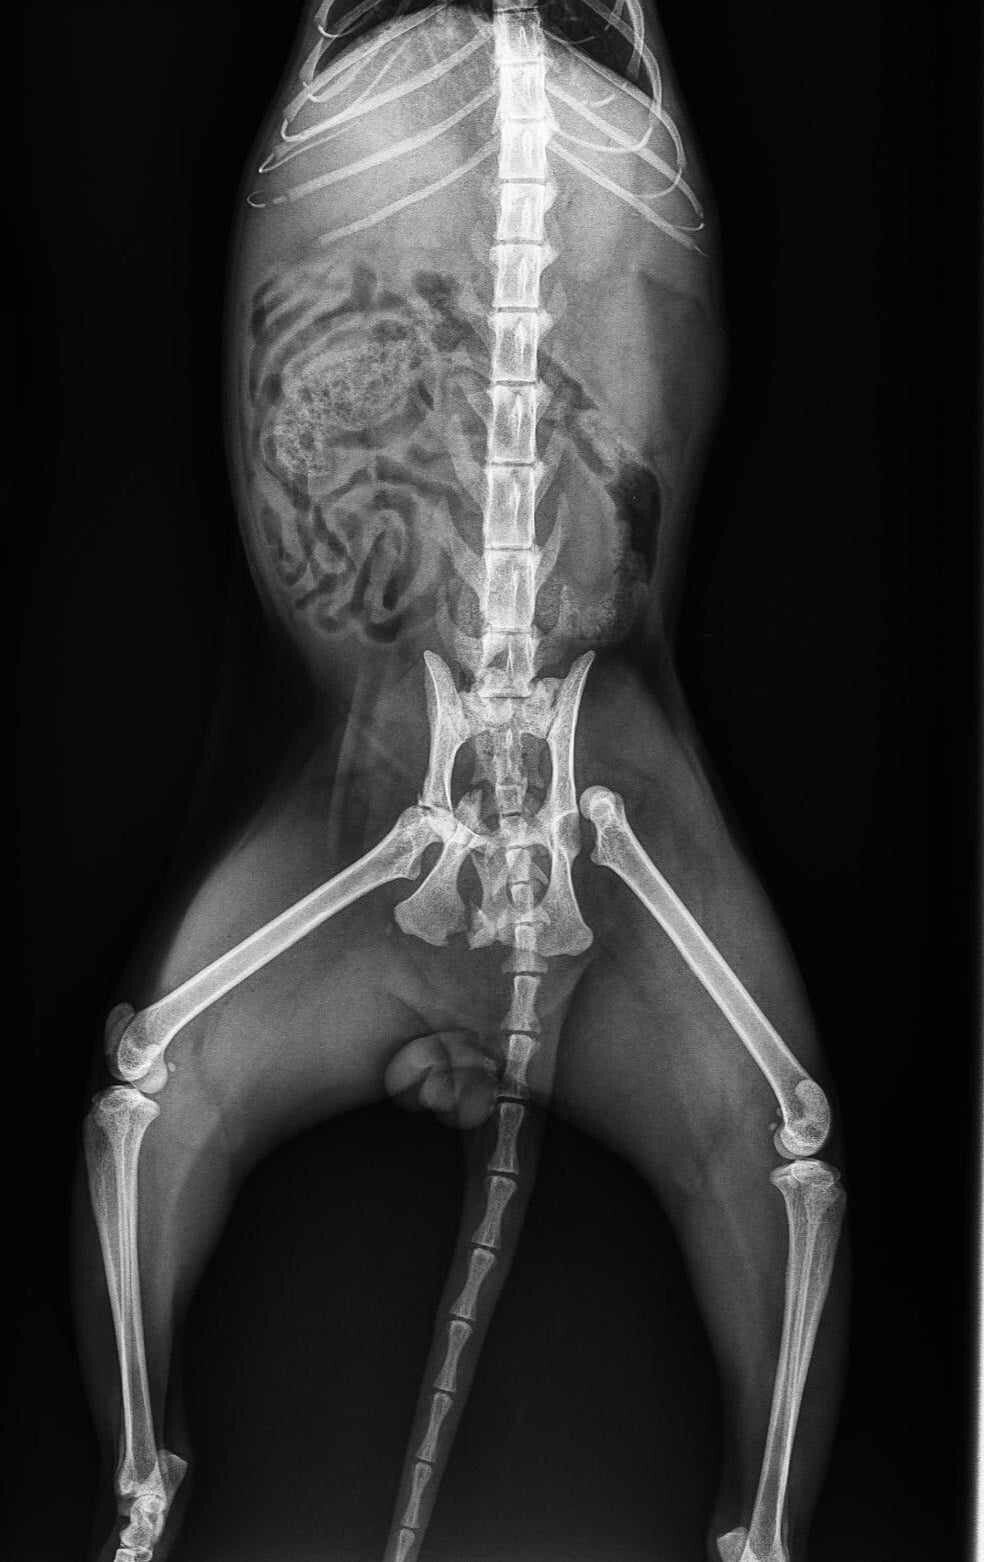

Liam bracht hem direct naar de Pro Vet Clinic in Plovdiv, waar uit onderzoek bleek dat de kat een gebroken heup en bekken had. Liam gaf hem de naam Riki.